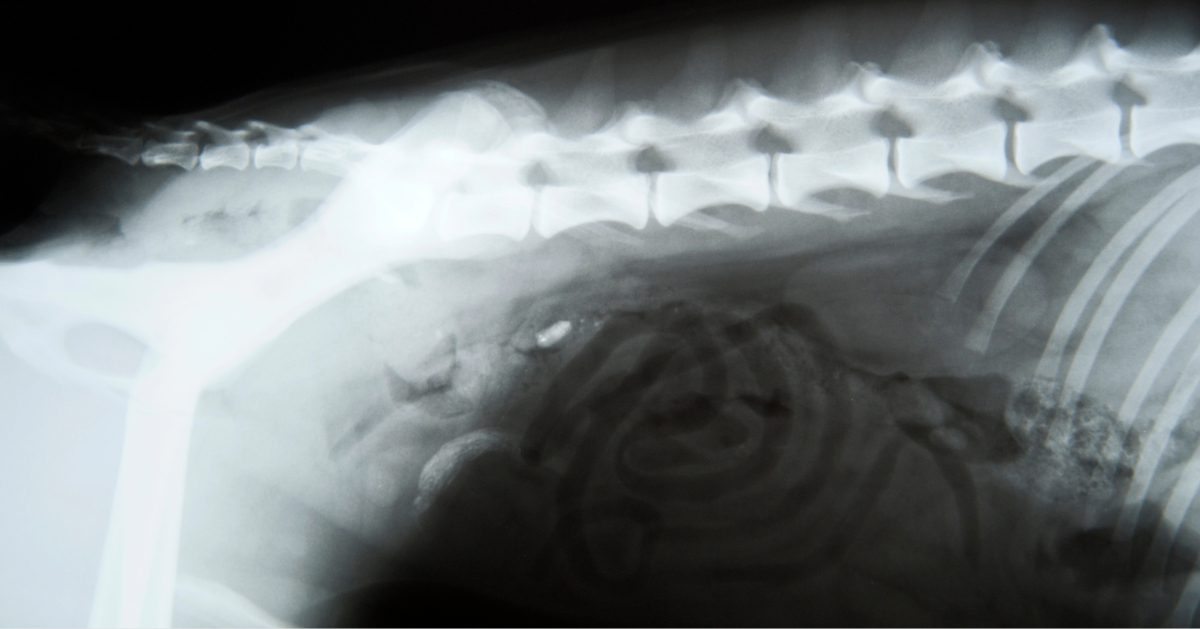

X-ray image of a dog's spine